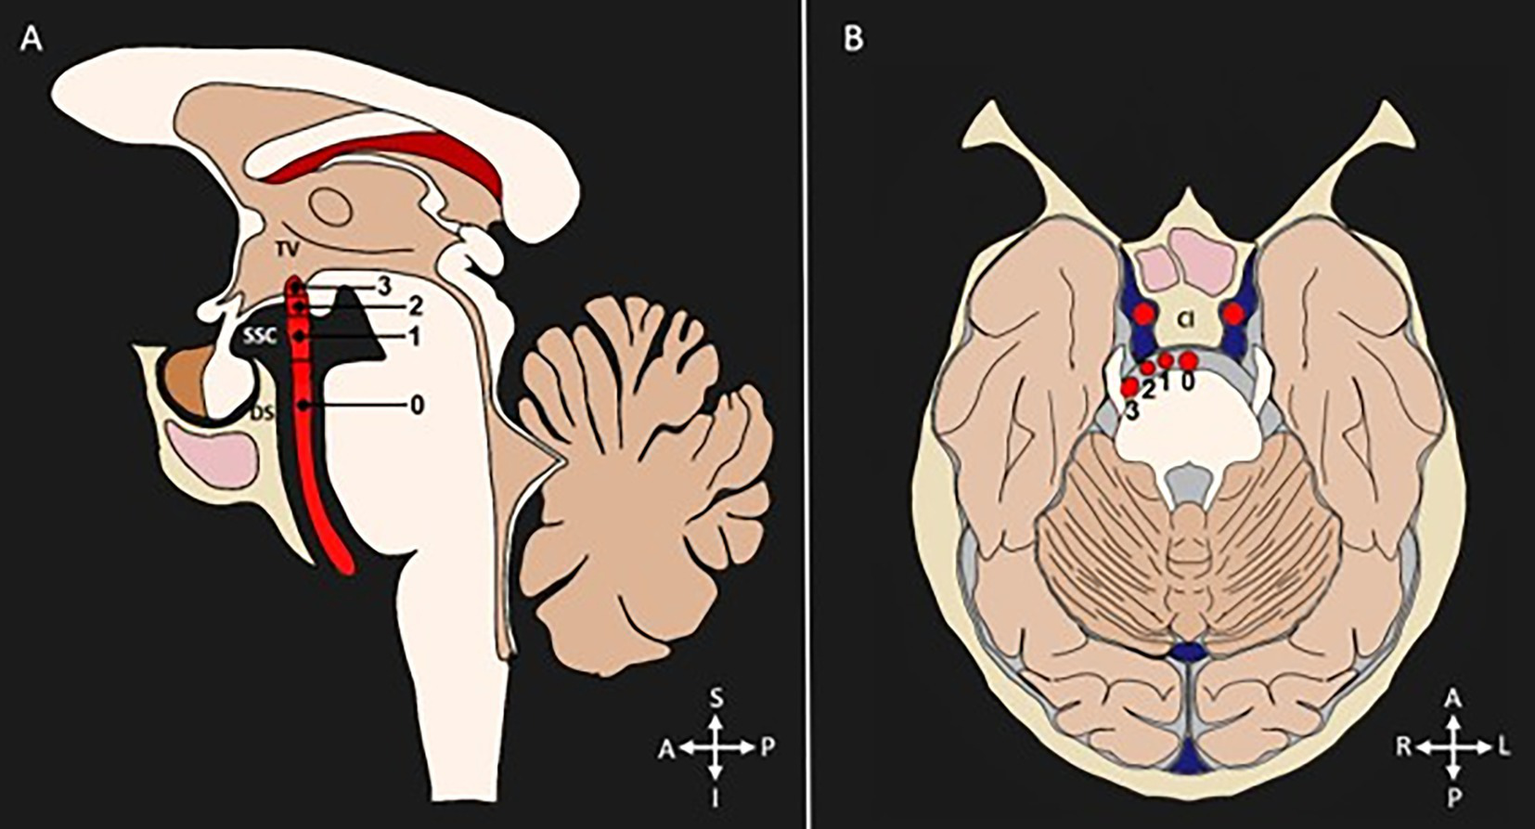

To detect the presence of tortuosity and VBD, most studies used the criteria established by Smoker et al. (13). This classification is based on the detection of two morphological aspects of the basilar artery: bifurcation height and laterality, each classified into four grades (grade 0 to grade 3), and a BA diameter ≥ 4.5 mm. The grades related to bifurcation are classified as follows: Grade 0: at the level of the dorsum sellae or below; Grade 1: in the suprasellar cistern; Grade 2: at the floor of the third ventricle; Grade 3: indenting the floor of the third ventricle. Regarding the laterality of the BA, the classification considers: Grade 0: in the midline; Grade 1: medial to the lateral margin of the clivus or sella turcica; Grade 2: lateral to the lateral margin of the clivus or sella turcica; Grade 3: in the cerebellopontine angle cistern. Figure 3 represents the Smoker criteria. Five articles used classifications based other variables, such as shape (16, 27) curve length (27), increases in length and diameter (17, 27), and BA angulation (15).

Figure 3. Diagnostic criteria for categorization of VBD. Diameter (≥4.5 mm). (A) Bifurcation height scores shown in a sagittal section: 0 = at level of dorsum sellae or below, 1 = in suprasellar cistern, 2 = at the third ventricle’s floor, 3 = indenting the floor of the third ventricle. (B) Lateral displacement scores shown in a transverse section: 0 = midline location, 1 = lateral to midline, and medial to the lateral margin of the clivus or sella turcica, 2 = lateral to the lateral margin of the clivus or sella turcica, 3 = cerebellopontine angle cistern location. TV, third ventricle. SSC, suprasellar cistern; DS, dorsum sellae; Cl, clivus; S, superior; I, inferior; A, anterior; P, posterior; R, right; L, left.